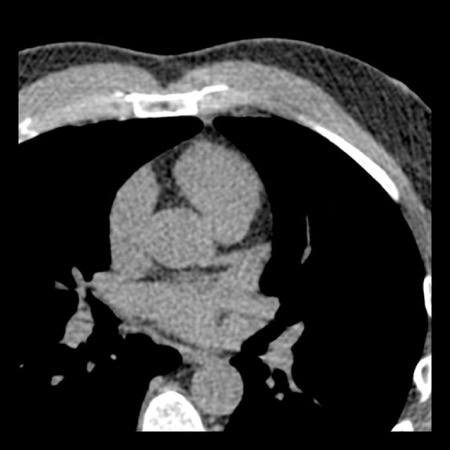

case 1 – CAD-RADS 2/P1

First, scroll through the scan.

Not all images are included. Some images without any abnormalities are skipped

from the series.

How would you describe the findings on the coronary CTA?

The findings are:

- Agatston score of

this patient was 14 (P1). Please, also note the calcification of the aortic valve. - Some partially

calcified and calcified plaques are present in the LAD with mild stenosis

(25-49%). - Calcified-plaque in

the LCX causing minimal stenosis (<25%). - Non-calcified

plaque in the distal RCA causing minimal stenosis (<25%). - This patient classifies

as CAD-RADS 2/P1, which means no further workup is needed.